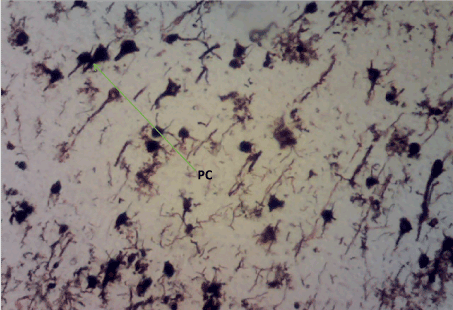

Bielschowskys silver stain: The Diabetic control group (Figure 11) shows distorted cell layer and degenerated pyramidal cells, Z. officinale treated diabetic group (Day 14) (Figure 12) shows distinctive cell layer and preserved pyramidal cells, Z. officinale treated diabetic group (Day 21) (Figure 13) shows distinctive cell layer and more preserved pyramidal cells, Metformin treated diabetic group (Figure 14) shows degenerated pyramidal cells and distorted cell layer [8].

Figure 13. Photomicrograph of the hippocampus of Group D showing more preserved pyramidal cells (PC). Bielchowskys Silver stain X100

Hippocampus: The hippocampus forms part of the limbic system and functions majorly in long-term memory and spatial navigation. Damage in any cell in the hippocampus can cause gross effects on the learning process of the individual. Astrocytes are most numerous glial cells in the brain and they help in the filling of spaces forming glial scars caused by neuronal damage and also help to repair the damaged cells that cannot be regenerated and a reduction in the number of these glial cells that help keep neuronal cells connected will cause a deficit in cell to cell connection. Figure 16 shows the normal hippocampus showing the different cell layers with no neuronal injury which is in support with the biochemical findings on free radicals and antioxidants. Figure 7 (Diabetic control) as compared to figure 6 (normal control) shows neuronal injury which was prominent throughout the granular layer which is in support with the biochemical analysis done on free radicals and antioxidants which shows elevated levels of free radicals and reduced levels of antioxidants proving low defence against free radicals which caused an increase in neurodegeneration and this was evident in the behavioural study. Diabetic control (Figure 11) shows degenerated pyramidal cells with short and disconnected processes and also has very few astrocytes with pericidal spaces. Figure 12 and figure 13 (Diabetes+ Z. officinale 14 and day 21) showed well preserved pyramidal cells in both groups. Figure 13 shows preserved neuronal cells as compared to that of figure 11, the astrocytes seen in figure 12 were numerous compared to that of the other groups which confirms the neuroprotective effect of Z. Officinale on brain cell and this finding is in agreement with, which observed that the administration of Z. officinale to diabetic rats increased astroglial response to injury which improved neurogenesis [9].